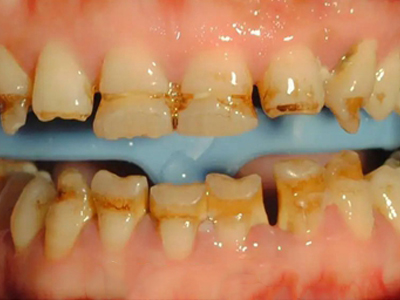

牙釉质发育不全牙表面上有坑图

牙釉质发育不全发展到严重时,导致牙釉质表面缺损,表现为带状、窝状的褐色凹坑,容易积存食物残渣诱发龋齿,表现为牙齿边上出现深褐色小洞。

牙釉质发育不全牙齿上棕色的坑图

牙釉质发育不全程度严重时,牙齿上出现较深的条状、点状凹陷,内含深褐色物质,并且牙齿尖端的牙釉质缺失,牙齿变得相对脆弱。